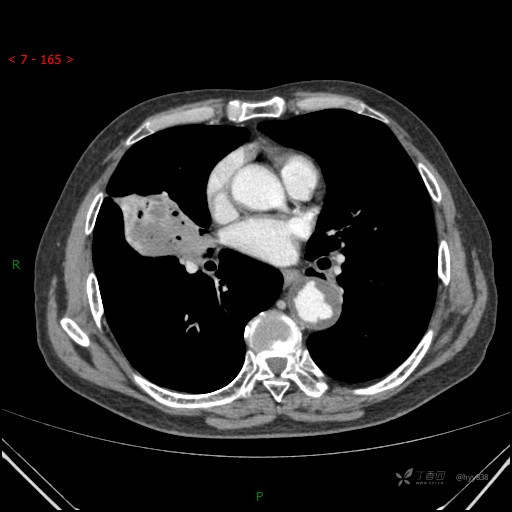

胸部CT肺窗

增强动脉期

静脉期